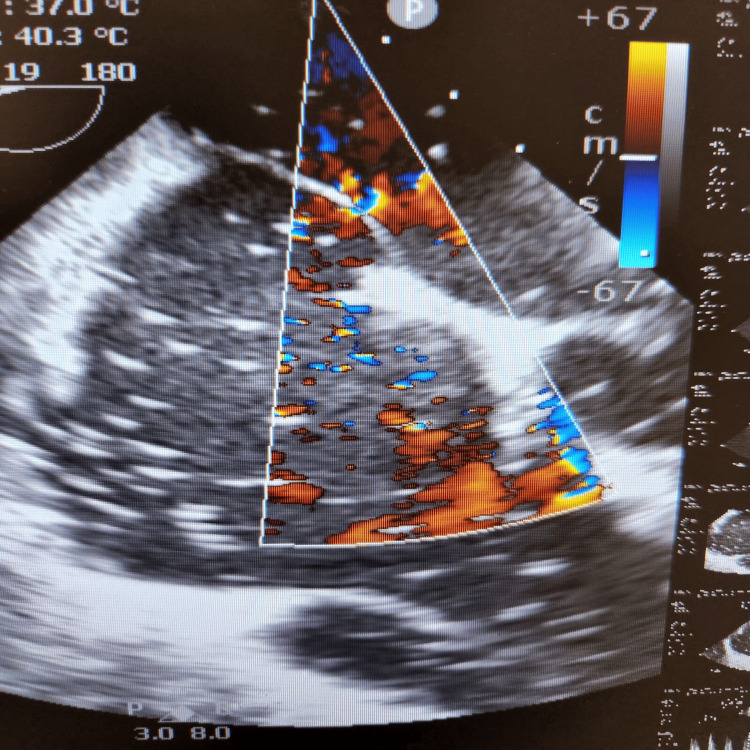

During the final stages of the ERCP procedure, a significant decrease in oxygen saturation and the emergence of irregular heartbeats were noticed. An intraoperative trans-esophageal echocardiogram (echo) revealed numerous air pockets in the right atrium, right ventricle, and left ventricle. Importantly, a patent foramen ovale was detected as shown in Figure 2, with indications of air bubbles (seen as white spots on 2D echo) passing through it into the left side of the heart as seen in Figures 3, 4. The patient was intubated in response to decreased oxygen levels while still in the operating room.

Gas embolism during ERCP is a rare but potentially fatal complication. It occurs when air enters the systemic circulation, leading to cardiovascular and pulmonary complications. One possible mechanism of gas embolism during ERCP is the intramural dissection of insufflated air into the portal venous system during endoscopic sphincterotomy [ref. 5]. In the presented case, the presence of a patent foramen ovale allowed for the passage of air bubbles from the right side of the heart to the left side, leading to systemic circulation and causing cardiovascular complications [ref. 2]. The patient’s case is unique because it involves a cardiac air embolism leading to difficulties during ERCP, which is an uncommon complication. The presence of a patent foramen ovale further complicates the situation, as it allows for the passage of air bubbles into the left side of the heart, increasing the risk of systemic complications.